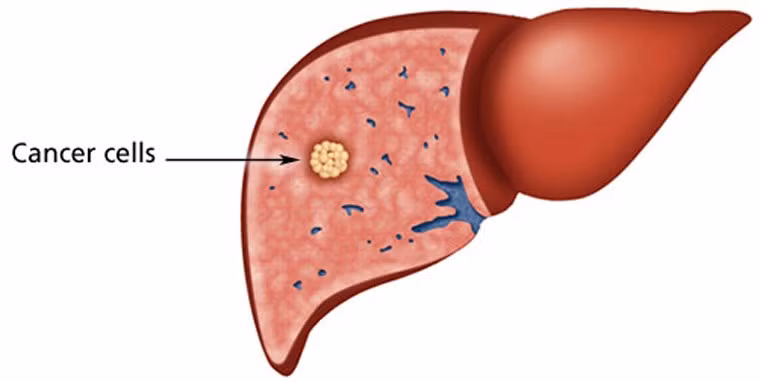

Ung thư gan: Là một trong những ung thư phổ biến nhất trên toàn thế giới. Nó là loại ung thư phát triển nhanh chóng và các triệu chứng bắt đầu xuất hiện ở giai đoạn muộn, do đó gây ra số ca tử vong cao vì căn bệnh này mỗi năm. Tính đến năm 2010, có đến 754.000 ca tử vong trên toàn thế giới.